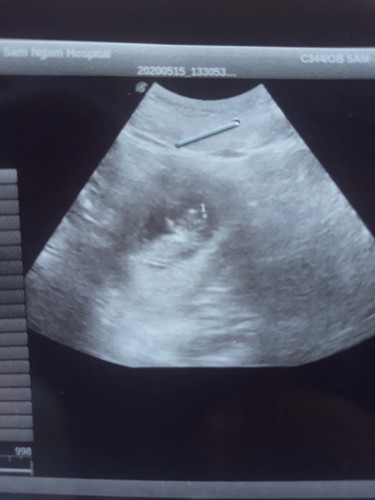

ท้องได้ 10w1d

หมอบอกน้องตัวเล็กมากค่ะ ต้องทำยังไงดีค่ะ